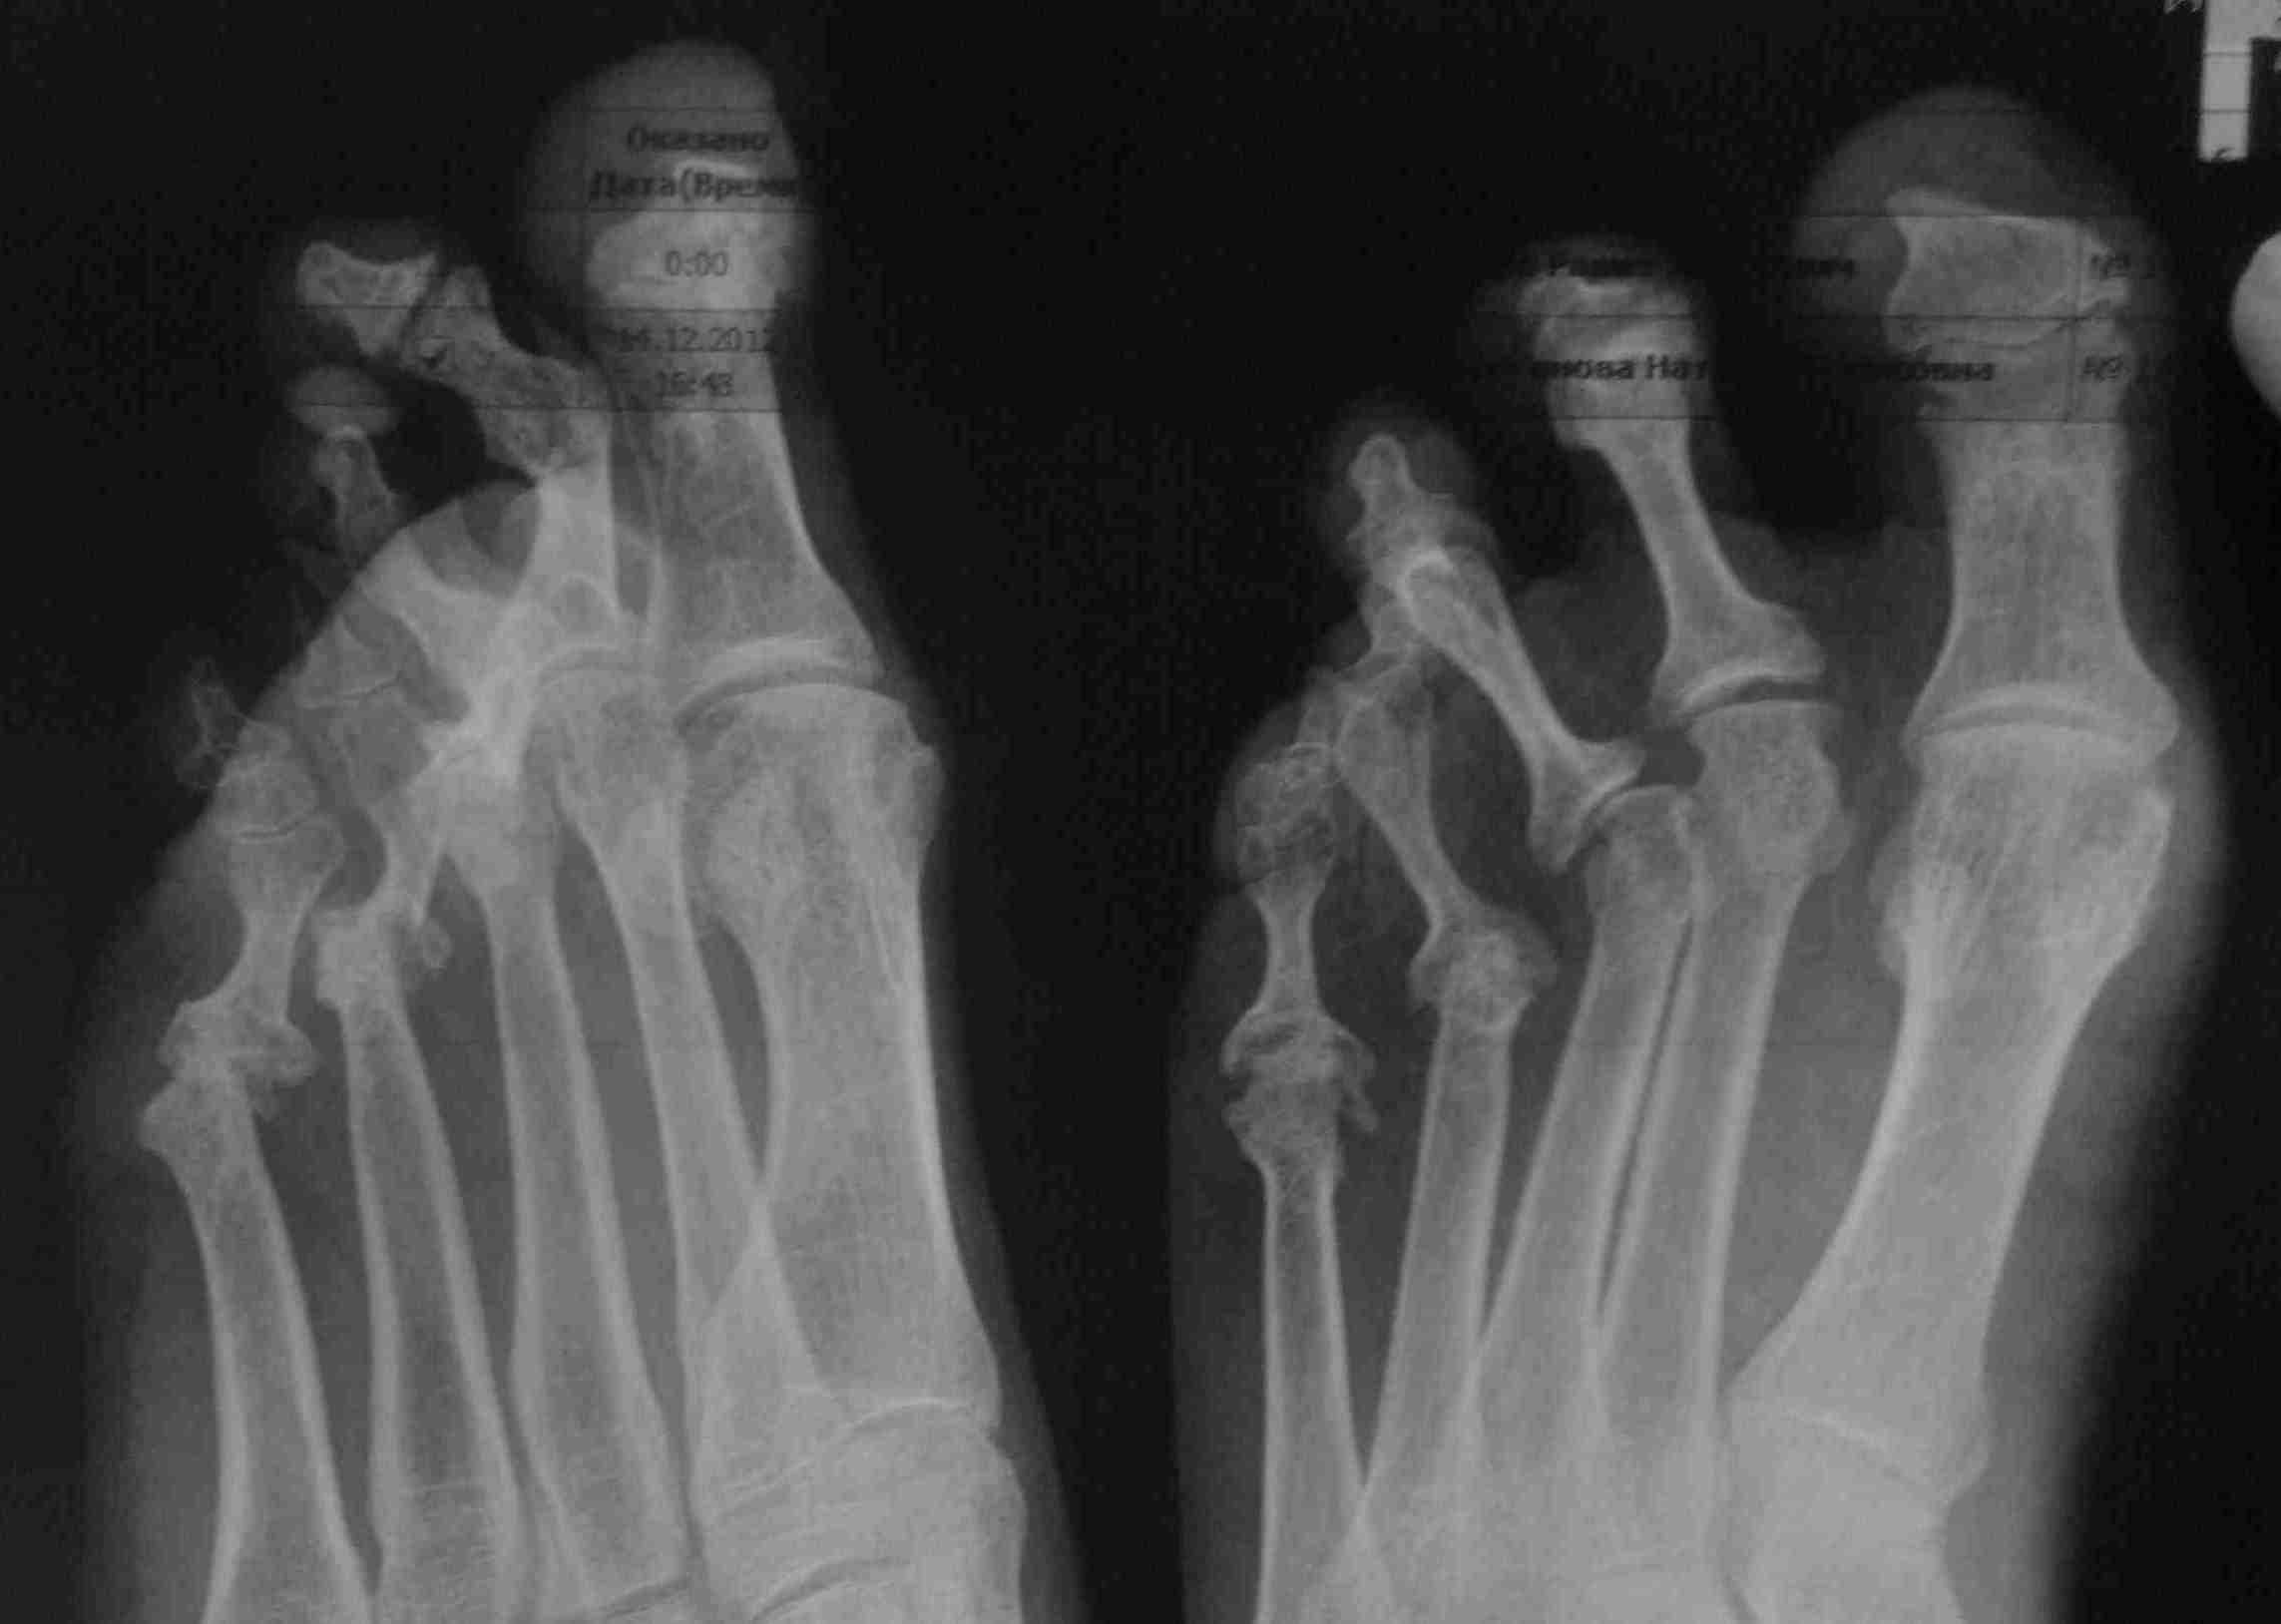

Стопа на фото. В анамнезе псориаз, но стопы, похоже, пострадали в результате подагры (заключение немецких коллег и аллопуринол помогает), пальцы так завернуло после одной атаки. Основные жалобы на деформацию 2-3, в межфаланговых суставах контрактуры фиксированные. Планирую резекцию головок основных фаланг 2-3 с временной фиксацией спицей. С плюснефаланговыми суставами что-то нужно делать? Другие варианты?

Резекция головок основных фаланг поможет устранить сгибательную контрактуру в проксимальных межфаланговых суставах. В результате пальцы станут торчком кверху? Ведь на тыльное сгибание в плюснефаланговых суставах и наружную девиацию пальцев предлагаемая Вами операция никак не повлияет. Без вмешательства на плюснефаланговых суставах никак не обойтись. Это может быть резекция оснований основных фаланг. Тогда можно обойтись меньшими доступами, совместив резекции проксимальной и дистальной части фаланги. Можно выполнить остеотомию Weil, или совместить Weil и основание фаланг, если по ходу вмешательства выясниться, что одной операции недостаточно. Опять же, нужно знать, есть ли натоптыши на подошве. Если есть - думать о Вейле. И еще насчет hallux hyperextensus. Сейчас переразгибание большого пальца не беспокоит? Возможно из-за более грубой деформации 2-3 пальцев. А если их выпрямить, большой палец не станет упираться в обувь? Обычно такая деформация - следствие тугоподвижности в 1 плюснефаланговом суставе. По снимку сустав вроде нормальный. А внешне - тугоподвижный. С чем это связано и не нужно ли с этим что-то делать? И еще насчет 4 пальца. Он деформирован и отклонен кнаружи, но это маскируется 3 пальцем. Выпрямите 2 и 3 - проявится деформация 4 пальца. Нужно быть готовым и к вмешательству на нем. К тому же уже имеется грубая артропатия 4 плюснефалангового, так что резекция одного из суставных концов не будет ему вредна.

На представленной Вами фотографии стопы видно, или, по крайней мере, кажется, что видно, что компонентами деформации второго и, особенно, третьего пальца являются тыльное сгибание в плюснефаланговом и подошвенное в проксимальном межфаланговом суставах. В таком случае, с помощью резекции головок основных фаланг (то есть, по сути, резекции проксимальных межфаланговых суставов) Вы добьетесь выпрямления пальцев в этих суставах. Но ведь на тыльное сгибание в плюснефаланговых суставах это не повлияет. Или повлияет? Если во время операции увидите, что палец выпрямился полностью - отлично. На этом и остановитесь. А если не выпрямится, тогда нужно будет что-то делать на уровне плюснефаланговых. К тому же очевидно, что третий палец отклонен кнаружи. Как на это отклонение повлияет резекция головки? Ведь вершина деформации расположена на уровне плюснефалангового сустава. Имеется и подвывих 3 пальца кнаружи. Значит тут и нужно вмешиваться. И вот в этой ситуации Weil и может помочь за счет укорочения плюсневой кости. Или резекция основания фаланги. А поперечное плоскостопие - это такое же словосочетание, как отложение солей. Помогает общаться на понятном языке с пациентом. Но само по себе ничего не значит, поскольку может включать в себя большое число совершенно разных ситуаций. Так что вопрос "Зачем Weil раз мы не лечим поперечное плоскостопие" не очень корректен. Вейля можно, например, применять при любом виде нестабильности плюснефалангового сустава. Как в этом случае.

Тут очень плохие 4 и 5 п/ф суставы - остеолиз головок пл. костей и подвывихи соотв. пальцев. 2 и 3 п/ф суставы на R-граммах смотрятся настолько более приличными, что, не видя фото и текста, скорее думалось бы о проблемах с латеральными пальцами. При подагре, что-то, мне таких стоп не попадалось. Наверное, в первую очередь, надо-бы разобраться с латеральной стороной стопы, которая как кажется, "тащит" за собой "соседей". Невзирая на "заключение немецких коллег и аллопуринол помогает" позвать своих ревматологов, как-то изучить кровоснабжение и иннервацию правой стопы, и не намечается ли симметрия слева. Homann`ов и Weil`ей наделать недолго и нетрудно, лишь бы не получилось потом как "в одном из медицинских центров"))))